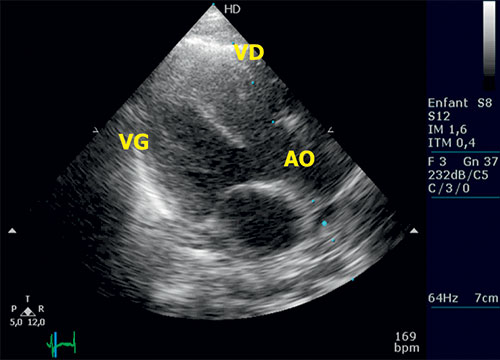

Fig. 11.6 ![]() Tétralogie de Fallot : échocardiographie transthoracique en grand axe parasternal gauche.

Tétralogie de Fallot : échocardiographie transthoracique en grand axe parasternal gauche.

Noter la large CIV (communication interventriculaire) de la partie haute du septum interventriculaire et l’aorte « à cheval » sur le septum, au-dessus de la CIV. AO : aorte ; VD : ventricule droit ; VG : ventricule gauche.